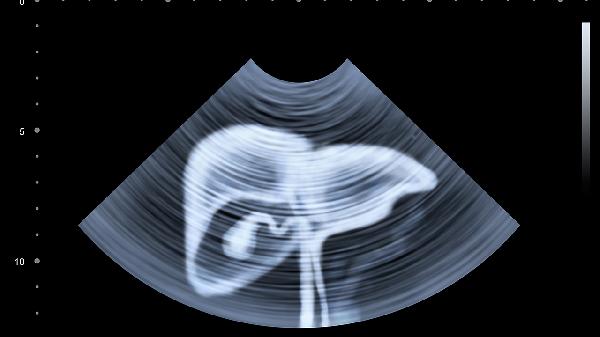

除饮食调节外,建议保持规律作息,避免23点后入睡以免影响肝脏排毒功能;每周进行150分钟中等强度有氧运动如快走、游泳,可改善肝脏脂肪代谢;严格限制酒精摄入,男性每日酒精量不超过25克,女性不超过15克;慎用不明成分的保健品,部分中草药如土三七可能引起肝窦阻塞综合征;定期体检监测肝功能指标,40岁以上人群建议每年进行肝脏超声检查。出现食欲减退、皮肤黄染等异常症状时应及时就医。